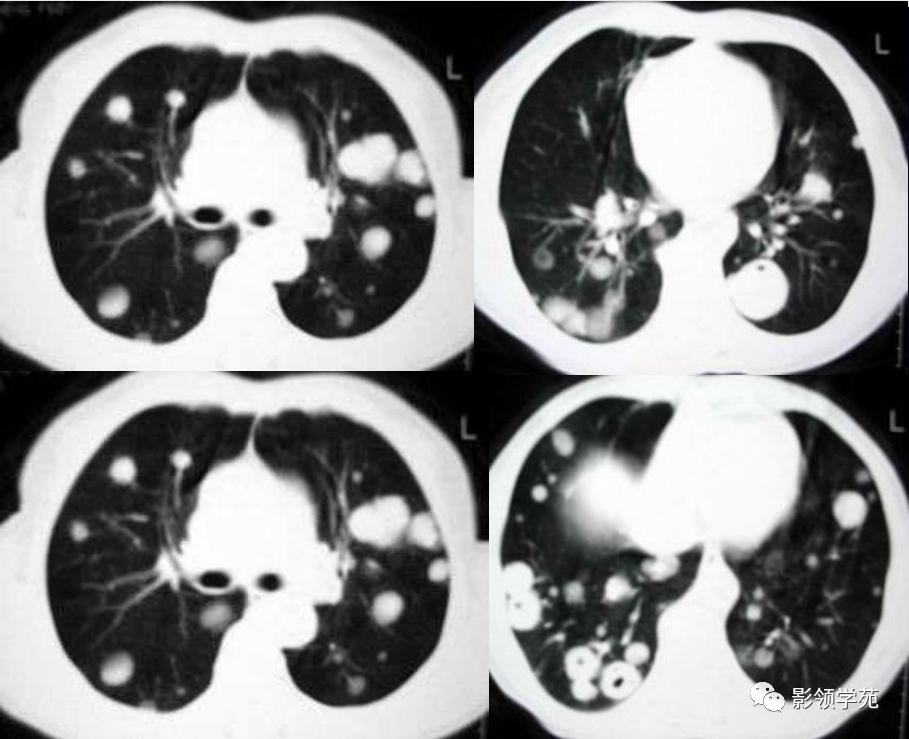

血行转移:双肺多发密度一致、大小形态不一结节状影(下图)

1. 血行性转移 :

多发或单发结节,大小不一,边缘较清楚。少数结节伴出血时出现晕轮征,即有略高密度影像环绕结节,使病变边缘模糊。病变有钙化常见于骨肉瘤或软骨肉瘤转移。转移瘤亦可表现为空洞。两肺多发的小结节影具有随机分布的特点,HRCT显示结节位于小叶中心、小叶间隔、支气管血管束及胸膜,结节大小不均匀。

肺转移瘤。肺窗像(A)示双肺野可见大小不等的圆形高密度结节影,纵隔增宽;纵隔窗像(B)示肺内肿块呈实性,纵隔满布大小不等的肿大淋巴结

CT诊断:甲状腺癌双肺多发转移